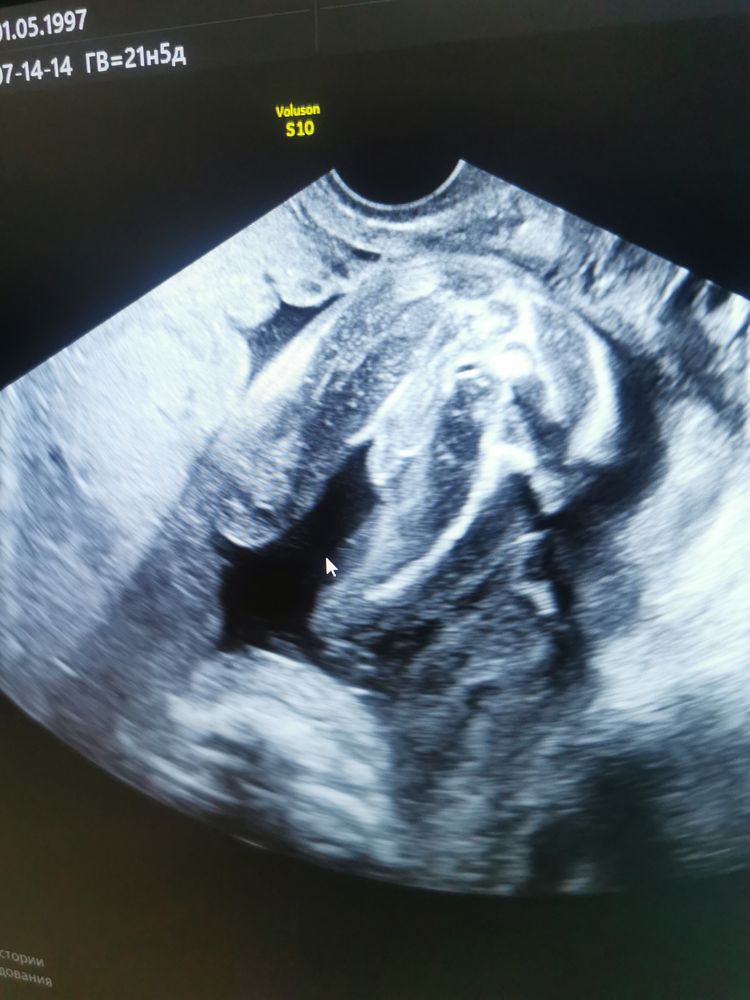

Он показывал писюн

У меня сохранилось фото дочери с того же ракурса на том же сроке 😄 да, действительно - не перепутаешь)))

УЗИ прилично так искажает размеры + там всё у них водянистое и после рождения спадёт. Но зато не придерёшься: мужчину видно 😊

Наш сразу всем сказал кто он есть 😂 Изображение и живот у меня тоже был не квадратный 😂 Изображение

Karmilla, ахахаха, да, я ещё на первом скрининге что-то заметила... И живот один-в-один!